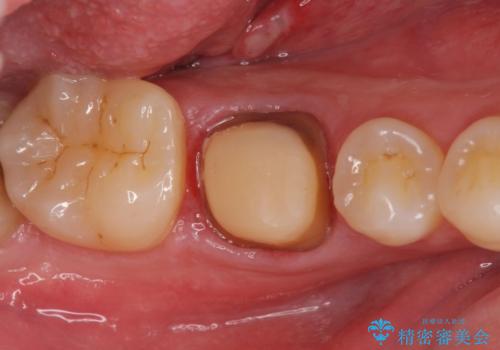

- 古い被せ物が取れたとの事で来院。

過去に根管治療がされている歯でしたが、現在症状はなく、レントゲンでも根尖病巣がないが根尖まで薬が到達していない状態でした。

そのまま被せ物だけやりかえるか根尖病巣の再発のリスクを考えて再根管治療を行うか患者様に決めて頂きました。

被せ物だけの治療を選択されましたのでジルコニアクラウンでの治療を行いました。